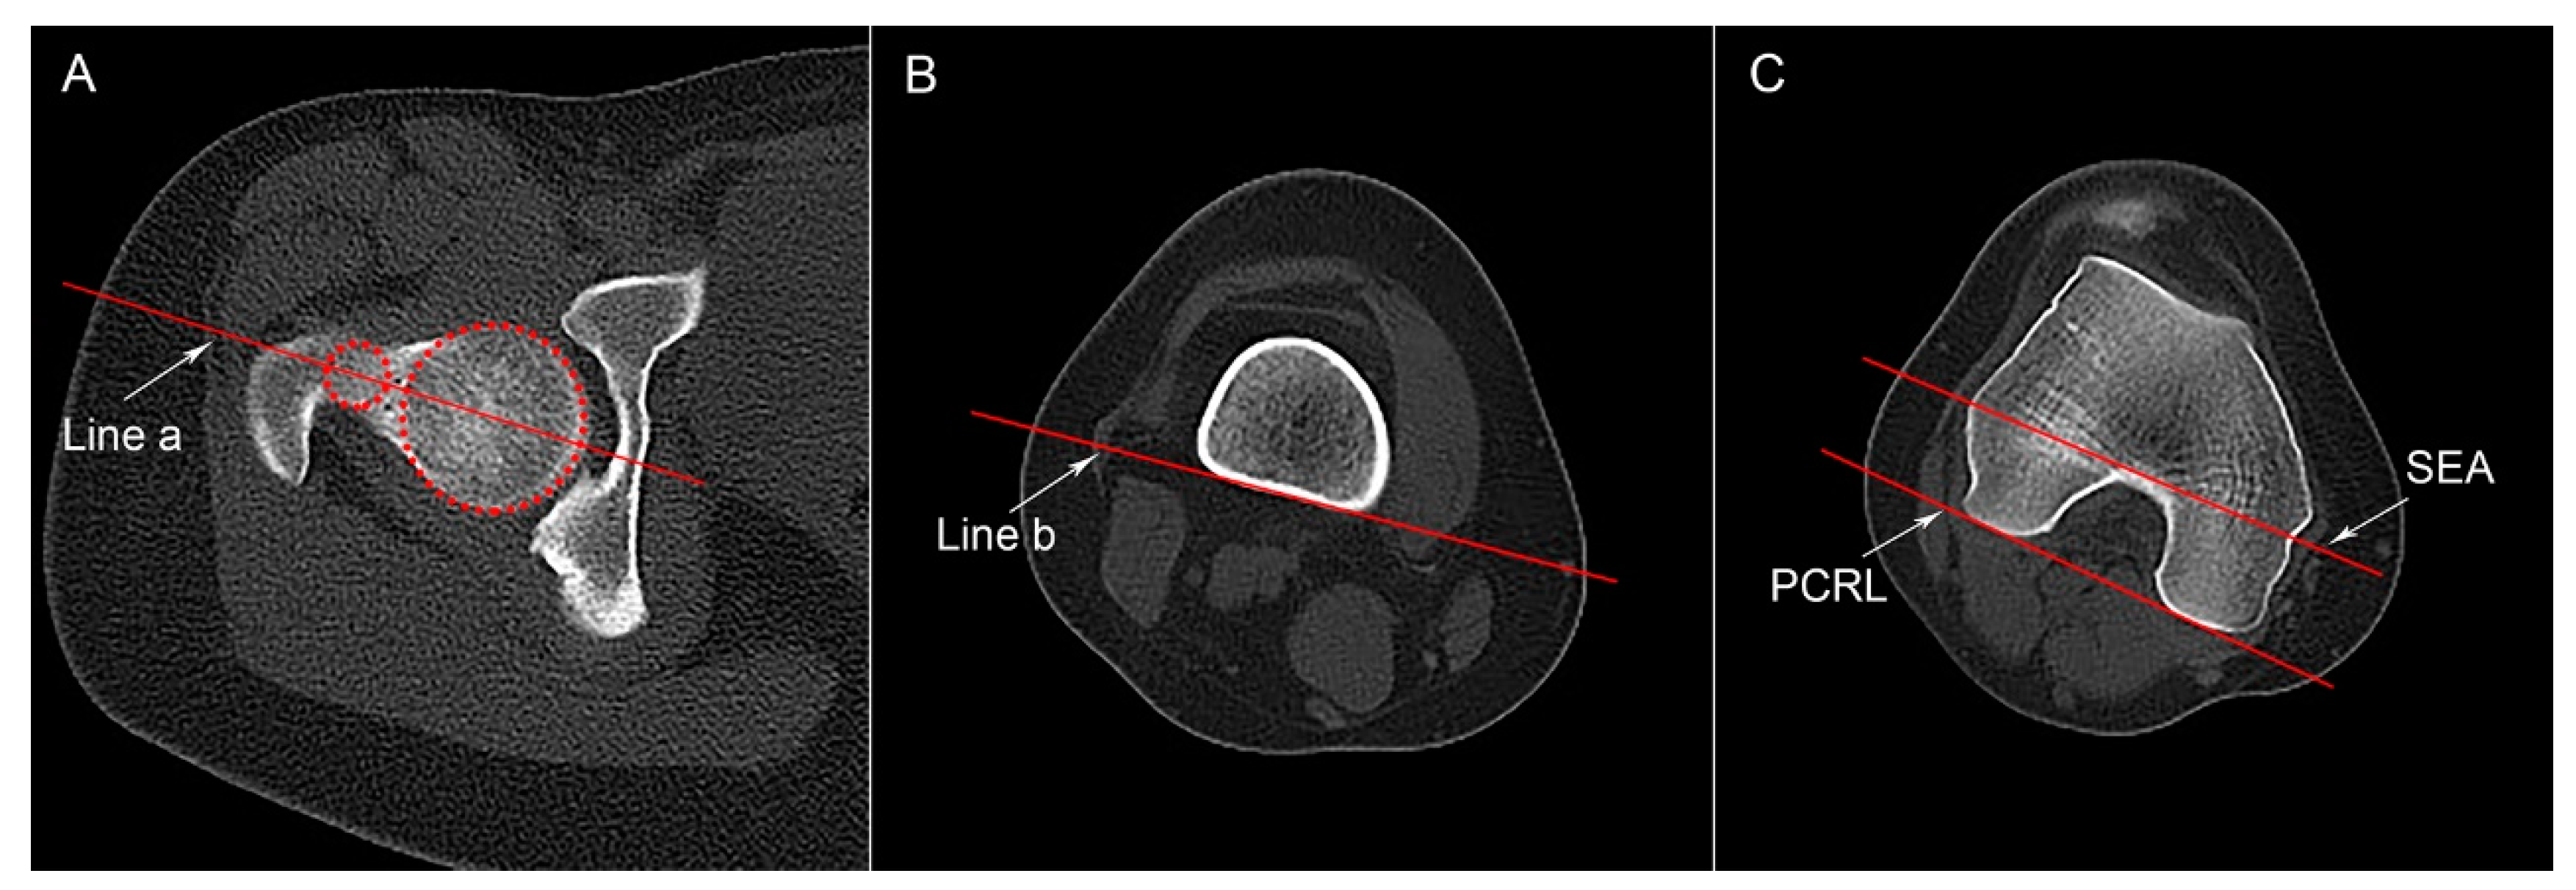

According to the method described previously, the segmental torsion parameters of the femur were measured by CT images [14]. Three different transverse slices of the femur were identified to draw four reference lines: a line a passing through the center of the femoral head and neck, a distal femoral shaft line, a posterior condylar reference line (PCRL), and the SEA (Figure 1). P-tAV (formed between line a and the PCRL) and S-tAV (formed between line a and the SEA) represent the total malrotation of the femur. The angle between the distal femoral shaft line and the PCRL (P-dAV) or the SEA (S-dAV) reflects the rotational malformation of the distal femur.

Figure 1.

Segmental femoral torsion parameters. (A) An axial CT slice showing the intact femoral head and neck is selected. The two circles were drawn to the margin of femoral head and neck to identify the center of the head and neck; Line a passes through the center of both the femoral head and the neck. (B) Distal femoral shaft line (Line b) is tangent to the posterior bony margin of the femoral shaft on the slice above the gastrocnemius insertion. (C) An axial slice showing an intact “Roman Arch” and the femoral condyles. The posterior condylar reference line (PCRL) was drawn tangent to the posterior femoral condyles; the surgical transepicondylar axis (SEA) passes through the sulcus of the medial epicondyle and the prominence of the lateral epicondyle.